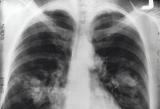

В 2020 году рак легких стал главной причиной смерти от онкологических заболеваний. По данным Всемирной организации здравоохранения, болезнь унесла жизнь 1,8 млн человек. Неудивительно, что специалисты бьют...

Исследование позволило установить 11 признаков и симптомов, наличие которых существенно увеличивает вероятность диагностики рака лёгких. Оно было основано на данных по нескольким десяткам тысяч человек...

Исследователи мониторингового проекта Global Burden of Disease определили, что за прошедшие десять лет смертность в связи с раковыми и прочими видами опухолей, которые поражают органы дыхания, ориентировочно снизилась на...

Американские учёные выяснили что случаи рака лёгких у некурящих людей, вызываются опухолями, возникшими в результате генетических мутаций. Ранее выдвигалась точка зрения о том, что эти опухоли...